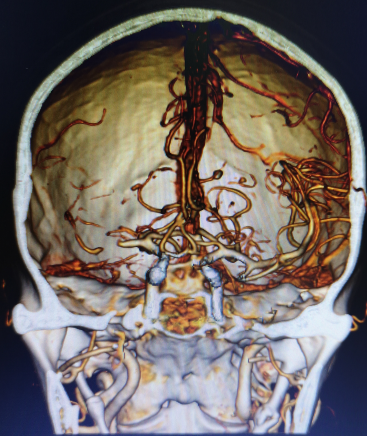

CTP:

右侧基底节区、颞叶、顶叶低灌注区域。